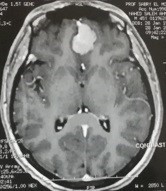

ورم بقاع الجمجمة بالفص الامامي

frontal lobe basement tumor

An image of magnetic resonance imaging with dye on the brain of a meningioma in the anterior chamber at the base of the skull before and after successful microscopic surgery to remove it.